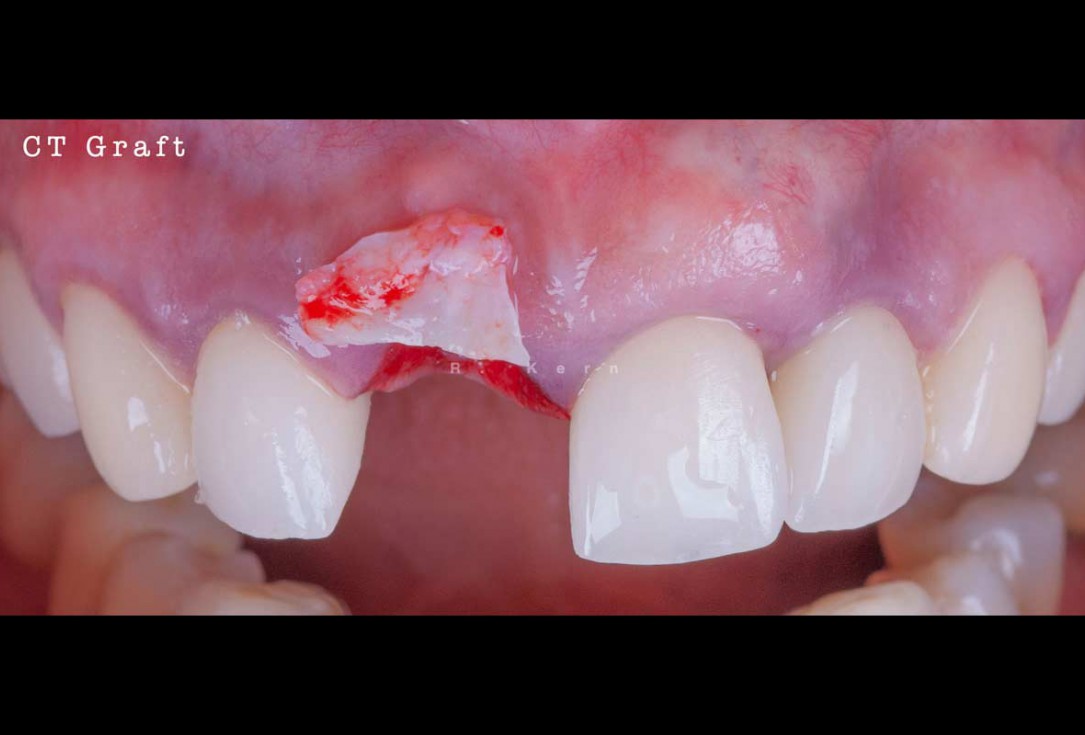

06/12 - Connective tissue graft in preparation for application

Immediate implant placement and periimplant bone augmentation using cerabone® - Dr. R. Kern